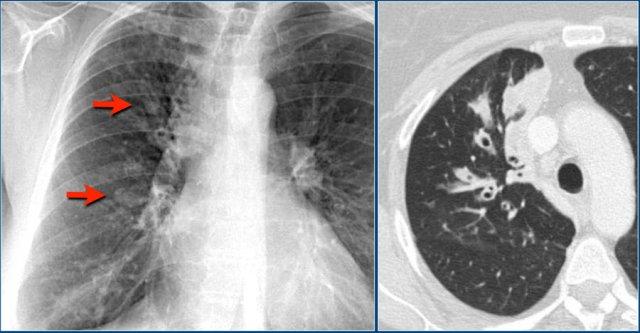

Trong trường hợp này, có một số cấu trúc dạng khối ở phổi phải.

CT đã chứng minh giãn phế quản kèm tắc nghẽn do nhầy.

Một biểu hiện phổ biến hơn của tắc nghẽn do nhầy được thấy ở đây.

Đây là hình ảnh điển hình ‘ngón tay trong găng tay’ của tắc nghẽn do nhầy.

Chất nhầy trong các phế quản giãn trông giống như các ngón tay trong một chiếc găng tay.